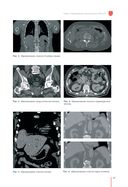

"Рекомендации по проведению стереотаксической лучевой терапии на аппарате "КиберНож" – это подробное руководство по вопросам необходимости применения стереотаксической лучевой терапии при различных злокачественных и доброкачественных процессах. Книга включает в себя детальное описание физико-технических особенностей роботизированной радиохирургической системы "КиберНож" и развернутые рекомендации по использованию аппарата для лечения различных онкопатологий и доброкачественных новообразований. Каждая глава снабжена клиническими примерами и планами лечения.